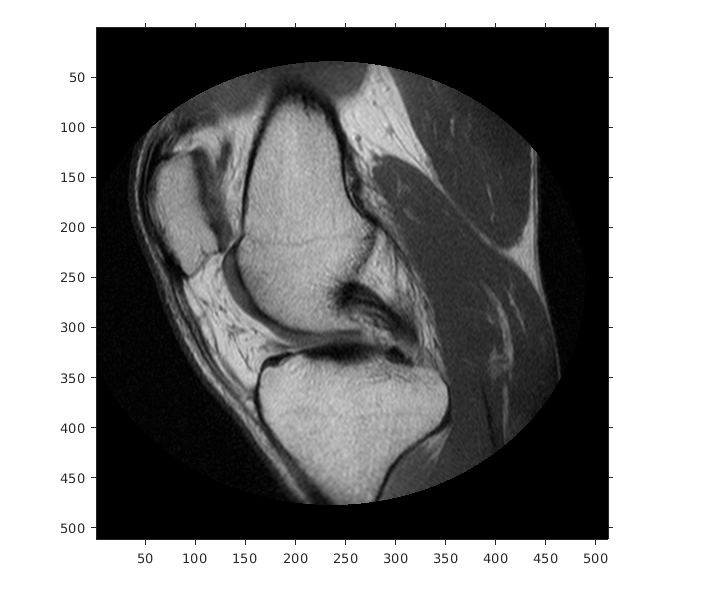

Отобразите изображение, не использовав пространственный объект привязки. Координаты осей отражают внутренние координаты. Заметьте, что координата (0,0) находится в левом верхнем углу.

figure

imshow(A,'DisplayRange',[0 512])

axis on

Figure contains an axes. The axes contains an object of type image.

Предположим, что вы хотите вычислить аппроксимированное положение и ширину колена в миллиметрах. Выберите конечные точки линейного сегмента, который запускается горизонтально через колено на уровне коленной чашечки. Например, используйте (x, y) точки (34,172) и (442,172).

xIntrinsic = [34 442];

yIntrinsic = [172 172];

Преобразуйте эти точки от внутренних координат до мировых координат.

[xWorld,yWorld] = intrinsicToWorld(RA,xIntrinsic,yIntrinsic)

xWorld = 1×2

10.6250  138.1250

yWorld = 1×2

53.7500   53.7500

Мировые координаты двух точек (10.625,53.75) и (138.125,53.75) в модулях миллиметров. Аппроксимированная ширина колена в миллиметрах:

width = xWorld(2) - xWorld(1)

width = 127.5000